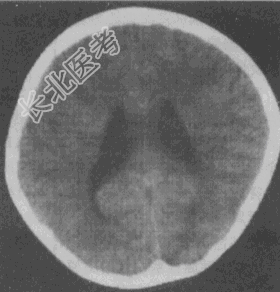

- 单项选择题男性,18岁。自幼出现阵发性抽搐伴意识不清, 每次持续数分钟。智力尚可。CT图像如图所示,影像学诊断应为

A、未见异常

B、脑积水

C、蛛网膜下腔出血

D、深部脑白质缺血

E、灰质异位